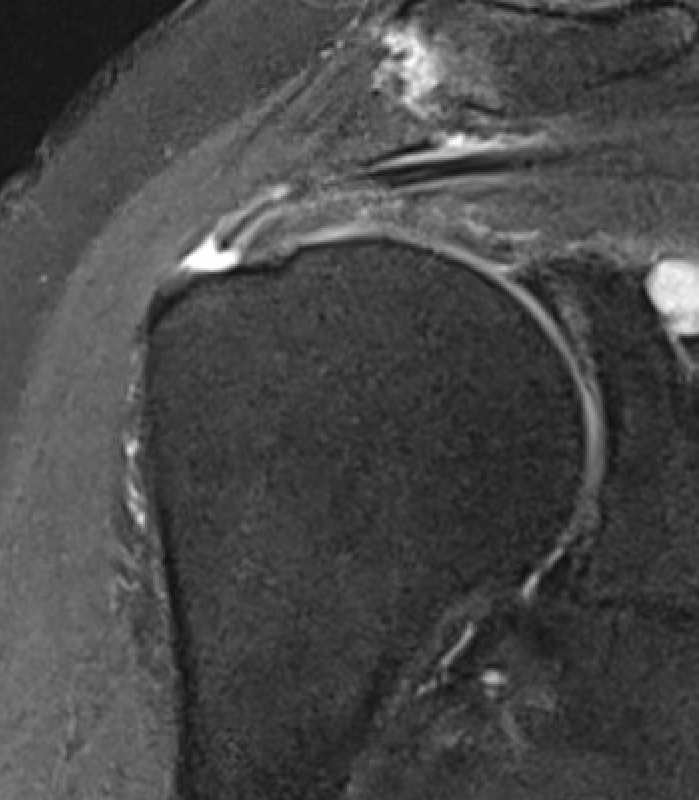

Small full thickness rotator cuff tear of supraspinatus - retracted to footprint

Large full thickness tear of supraspinatus and infraspinatus tendon - retracted to midhumeral head

Massive rotator cuff tear of the supraspinatus and infraspinatus tendon - retracted to glenoid